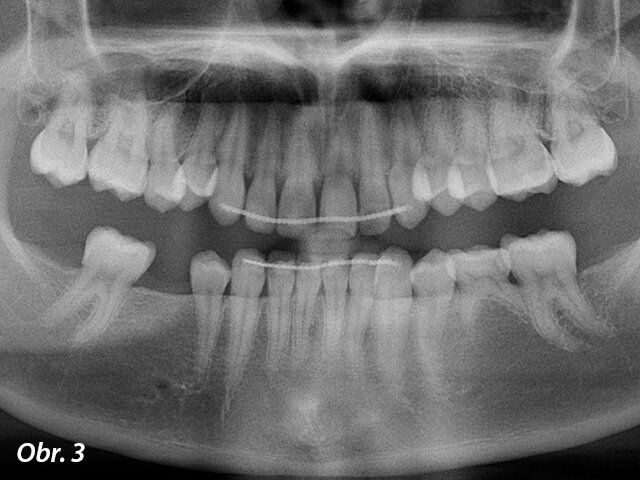

Dolní zuby pacientky před ošetřením.